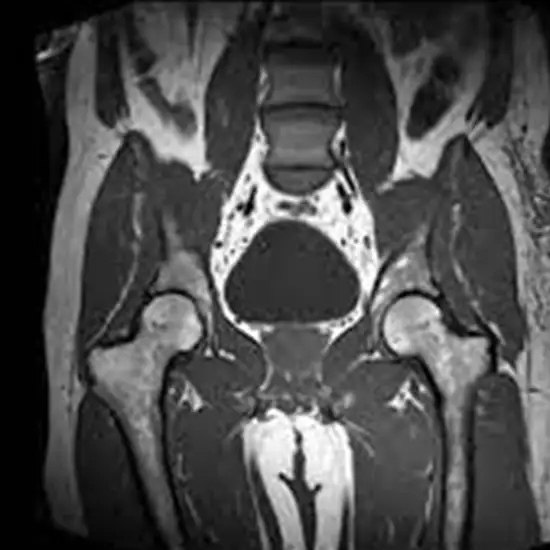

An MRI of the pelvis provides a comprehensive analysis of the anatomical structures and organs in the pelvic area, which extends from the belly button to the groin.

MRI (Magnetic Resonance Imaging) screening of the pelvis is a non-invasive radiology test used to evaluate the condition of the pelvis and surrounding tissue. MRI screening of the pelvis is done to look for its condition and surrounding area.